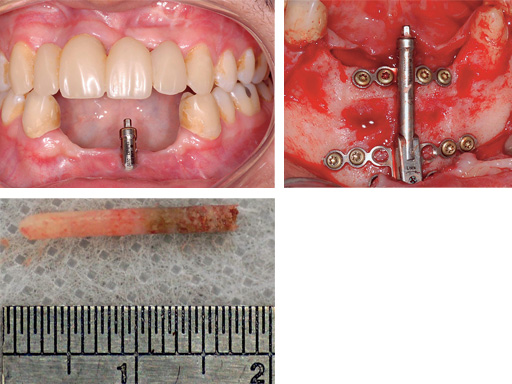

Mandibular distraction in a 20-year-old male after trauma. The bone biopsy shows a darker shading where the bone is newly formed.